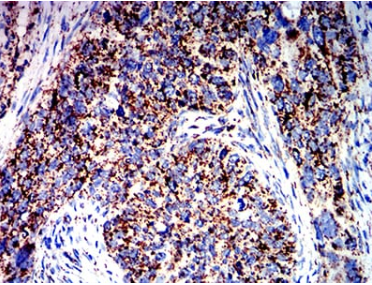

| AC1212 | ATPIF1 Mouse Monoclonal antibody[1F3B8] | 100ug | $367 | 10days |

| AC1212 | ATPIF1 Mouse Monoclonal antibody[1F3B8] | 200ug | $660.6 | 10days |